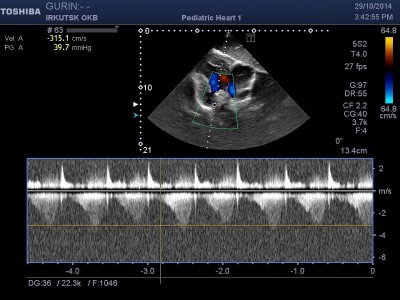

"Единственная надежда осталась у меня на Вашу помощь . Моего ребеночка зовут ГУРИН АЛЕКСАНДР ЕВГЕНЬЕВИЧ 07.02.2008 Г/Р,проживаем мы в городе Братске, Иркутской области, ул. Войнов-интернационалистов д13-кв.38., меня зовут Гурина Светлана Александровна, вот и вся наша семья!! Экология в нашем городе все больше и больше влияет на наше здоровье, не прошло и мимо нас!!!! У моего сыночка страшный диагноз : ВПС, единый желудочек сердца, транспозиция магистральных сосудов, ДМПП вторичный и совсем недавно выявлена еще и недостаточность митрального клапана 3ст.Легочная гипертензия, которая не дает моему сыну нормально жить!!!!!Диагноз нам поставили на четвертом месяце после рождения, но подозрение на порок были уже на второй день его жизни! хотя всю беременность я отходила без каких либо отклонений! Каждый год мы планово посещаем областной центр в городе Иркутске и вот только сейчас врачи выявили желание прооперировать его , но при больших страхах. В моей жизни не было слишком много счастливых моментов, но никогда прежде я не была так счастлива когда у меня появился мой малыш!Узнав о клинике в Германии, чьи врачи делают действительно чудеса, я обратилась за консультацией именно к ним, зная что в России таких деток оперировали не много, и что чаще всего результат заканчивался трагично! На мое письмо они ответили сразу, и как только они получили результаты последних обследований, то естественно согласились, понимая, что наша ситуация не из лучших! Но к сожалению таких средств мне самой никогда не найти, даже если все продать, хотя продавать то мне собственно и нечего!!!Разве что свою жизнь в обмен на жизнь своего ребенка! Я не работаю, так как не один работодатель меня не хочет держать, сыночек потому что очень часто болеет, из целой недели мы ходим в садик максимум три дня! а садик для него это единственное место, где он может пообщаться со своими сверстниками! Поэтому сижу дома по уходу за ребенком - инвалидом!Весь доход составляет 21850 рублей в месяц, при том условии что я снимаю квартиру за 10000рублей,так как своей не имею.

Добавлен выписной эпикриз Новосибирский НИИ кровообращения имени Е.Н.Мешалкина